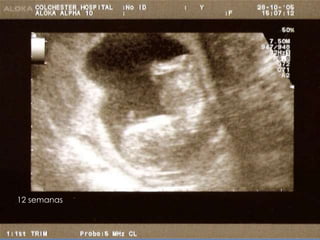

12 semanas